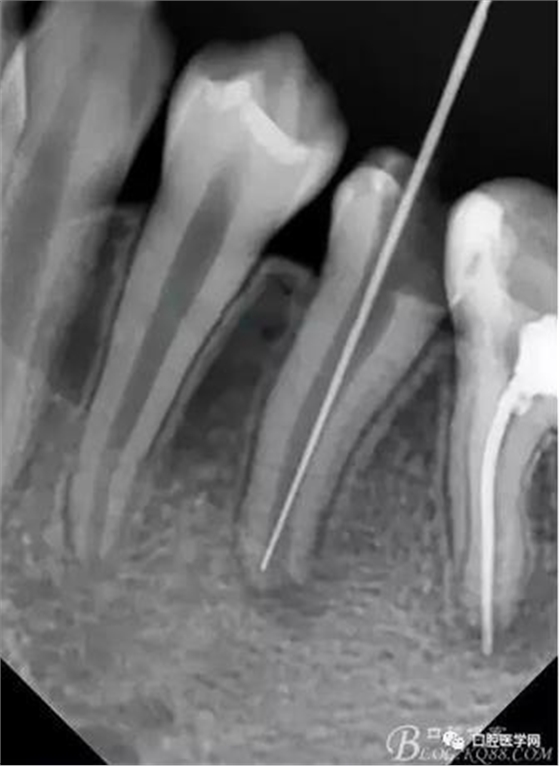

在拔髓的過程中遇到流血,但是不會疼,根管腔超級大,40#根管挫完全不用加壓就直接掉到根尖部,測長直接報警,嚇了一跳,根尖孔這么大,40#根管挫很輕松就超出根尖孔。

擔心超出根尖孔破壞根尖組織,及時測長再加一張X片,如下圖:

小心翼翼的控制根管長度后進行根管預備,3%雙氧水與生理鹽水交替沖洗,吸潮紙尖吸干,行氫氧化鈣根管充填,氧化鋅丁香油暫封,醫(yī)囑2周復診。